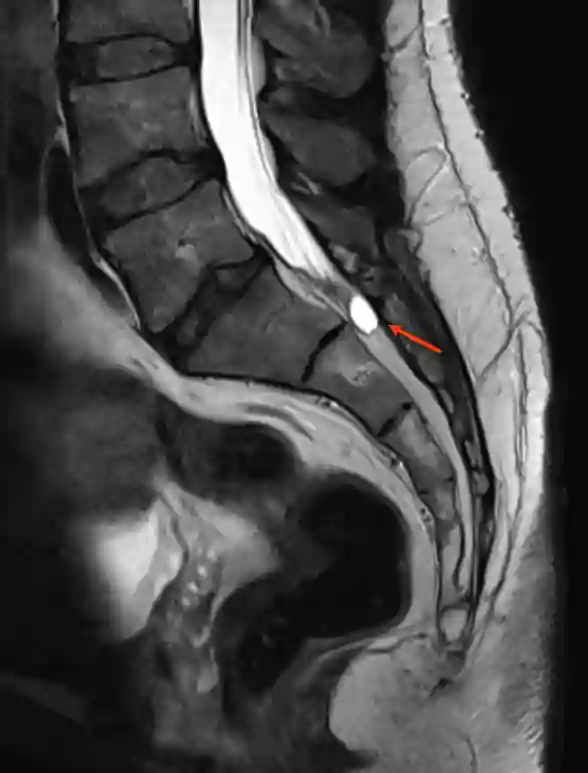

Tarlov Cyst T2 Sagittal MRI

Illustration of a Tarlov cyst (red arrow) in the sagittal T2 MRI image.